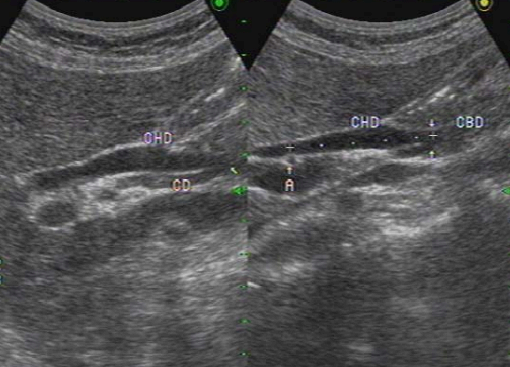

총담관(CBD) 확장 시 간동맥 (hepatic artery) 이 보이는 단면에서 wall 은 제외하고 측정한다. 총담관을 측정할 때 간동맥은 랜드마크가 된다.

2) 정상 직경 및 초음파 특징소견

- 총담관(common bile duct)의 직경은 7mm를 초과하지 않는다 (예외: 고령자, cholecystectomy 인경우 7~11mm 정상으로 간주한다.)

- 총 간관(common hepatic duct)은 4mm보다 작다.

- 간외담관(extrahepatic bile duct)은 총 간관(CHD)과 총담관(CBD)으로 나뉘고 그 끝은 십이지장 내 유두부이다.

extrahepatic bile duct 3) 지방식 (fatty meal)